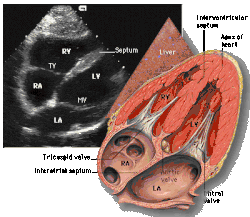

![]() Subcostal four chamber |

![]() Apical four chamber |

| Each figure contains a TTE with a black background, and a corresponding colored illustration. | Patrick J. Lynch and C. Carl Jaffe, Yale University, 2006. | ||||||||||

| Click on a figure to enlarge it and see some parts of the heart identified. RV, right ventricle; LV, left ventricle; RA, right atrium; LA, left atrium; TV, tricuspid valve; MV, mitral valve; AV, aortic valve; RVOT, right ventricular outflow tract; LVOT, left ventricular outflow tract | |||||||||||